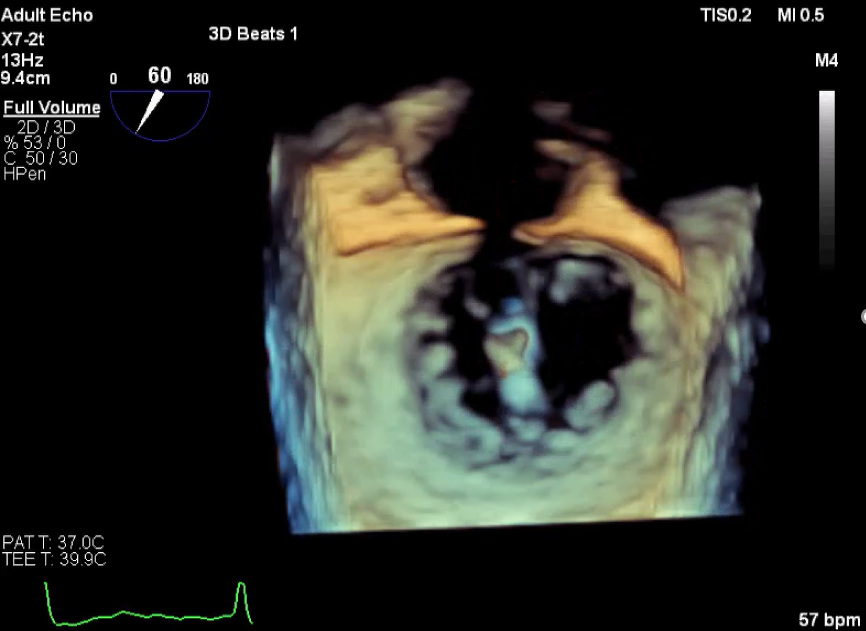

3D视图打开夹子

3D视图下观察二尖瓣双孔形态

3D-color:残余少量返流